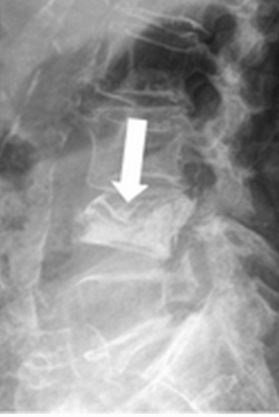

The authors set out to evaluate technical success of image-guided elastoplasty – a novel method for percutaneous vertebral augmentation with a silicone elastomeric material. The procedure was successfully performed 19 times which led the authors to say elastoplasty seems to be a safe procedure that provides effective pain control.

Article: Safety and results of image-guided vertebroplasty with elastomeric polymer material (elastoplasty)